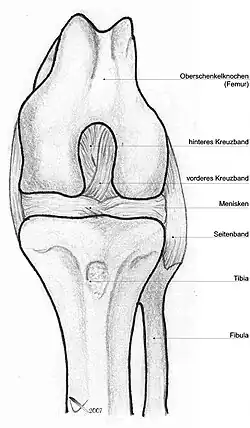

Bänder

Da das Knie durch seine knöcherne Konstruktion sehr instabil ist, wird es durch zahlreiche Bänder gesichert. Sie verstärken damit die Gelenkkapsel, in deren äußere Schicht sie in der Regel eingebaut sind. Die Bänder des Knies werden nach ihrer Lage in vordere (ventrale), seitliche (kollaterale), hintere (dorsale) und zentrale Bänder eingeteilt.

Seitliche Bandsicherung

Das Knie hat zwei Seitenbänder: ein inneres (Ligamentum collaterale tibiale) und ein äußeres (Ligamentum collaterale fibulare). In Streckstellung sind beide Seitenbänder (auch Kollateralbänder genannt) gespannt und verhindern somit die Drehbewegung, in Beugestellung verkleinert sich der Krümmungsradius, Ursprung und Ansatz nähern sich einander an und die Bänder sind infolgedessen entspannt. Beide Seitenbänder stabilisieren das Kniegelenk in seitlicher Richtung (Frontalebene), damit ein Wegknicken in eine O-Bein-Stellung (Genu varum) oder X-Bein-Stellung (Genu valgum) verhindert wird.

Zentrale Bandsicherung

Die Kreuzbänder (Ligamenta cruciata) ziehen von der Grube zwischen den Oberschenkelknorren zum Schienbein. Von der Seite und von vorn betrachtet überkreuzen sie sich dabei in ihrem Verlauf.

Menisken

Da die miteinander in Verbindung stehenden (artikulierenden) Gelenkflächen nicht genau aufeinander passen, wird diese „Ungleichheit“ (Inkongruenz) durch halbmondförmige Faserknorpelscheiben, die Menisken ausgeglichen, die den Drehbewegungen folgen können. Eine weitere Aufgabe der Menisken besteht in der Vergrößerung der Kontaktfläche zwischen Schienbein und Oberschenkelknochen.

Man unterscheidet einen Innenmeniskus (Meniscus medialis), der C-förmig, größer und etwas unbeweglicher (da mit dem Innenband verwachsen) ist, und einen Außenmeniskus (Meniscus lateralis), der kreisförmig, kleiner und beweglicher ist (da er mit keinem Seitenband verwachsen ist). Die Menisken sind im Querschnitt keilförmig. Die hohe Kante liegt außen, die niedrige innen. Da die Oberschenkelknochen genau in der Mitte direkt auf dem Schienbeinplateau und peripher auf den Menisken aufliegen, tragen diese einen wesentlichen Teil der Last.